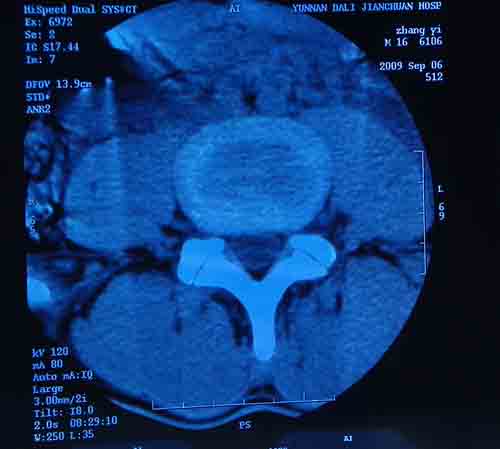

腰5/骶1椎间膨突出外,还有点异常,不知是什么东东,请各位大虾帮忙看看(12骨窗最明显)